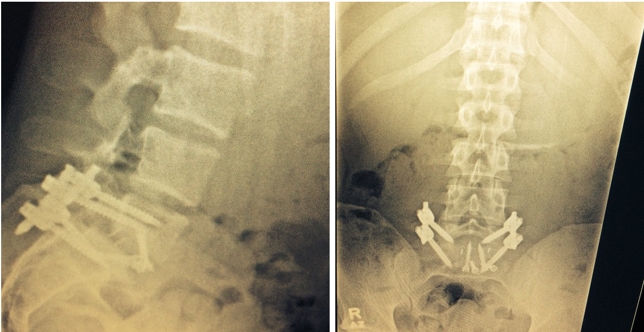

Mutante também divulgou imagens de suas radiografias nas redes sociais. Foto: Reprodução

Tudo bem, meus amigos? Eu quero compartilhar uma história com vocês. Estou muito orgulhoso de mim e me sinto um vencedor. Venci minha principal luta, que era contra mim mesmo. O fato de chegar apto a lutar ontem já me faz um vencedor. Não quero dar desculpas para derrota, nunca fiz isso e agora não seria a primeira vez. Inclusive, quero parabenizer o Sam Alvey. Ele absorveu bem meus golpes e conseguiu virar o jogo. Mas a vitória que tive foi a que Deus me permitiu de voltar a trabalhar, e estou muito feliz e grato por isso. Pouco mais de cinco meses atras, eu tive uma grave lesão na coluna lombar. Essa lesão já me incomodava há mais de 10 anos, e os últimos dois anos da minha vida eu passei dormindo sentado. Se dormisse em qualquer outra posição, eu não andava no dia seguinte. Durante minha luta contra o Andrew Craig, minha vértebra se deslocou ainda mais e, por isso, alguns dias depois, minhas pernas estavam quase que paralisadas. Tive que fazer uma cirurgia de emergência, e o procedimento foi feito pela minha barriga. O médico removeu o disco danificado entre L5 e S1, colocando uma prótese e fixando-a com quatro parafusos. Na mesma cirurgia, foram colocados mais quatro parafusos e duas hastes pela parte posterior, para então concluir a artrodese. Foram 7h de cirurgia. Três meses depois, quando já estava tudo calcificado e cicatrizado, o médico me liberou para treinar. Começava então minha guerra interna, com meu corpo e mente. Por diversas vezes, eu sai da academia chorando pela tentativa frustrada de tentar fazer uma sombra de boxe, movimentos simples para qualquer lutador, e não conseguir por conta da dor e rigidez no local. Pensei em desistir por diversas vezes, mas sabia que tinha que vencer minha batalha particular. Fiz de tudo para voltar em alto nível, lutando contra meus maus pensamentos, que me diziam ‘você já era’. Eu ia todos os dias até academia, mesmo que fosse pra treinar por 10 minutos ou ficar apenas olhando o treino. Foquei, a vontade de vencer foi maior que o medo de perder e fui melhorando. Então, tive uma grande inflamação sacroilíaca, uma espécie de efeito colateral da cirurgia de artrose, que limitava meus movimentos. Eu mal conseguia abaixar para calçar os sapatos. Voltei ao médico e ele disse que não seria difícil resolver meu problema. Seria necessário fazer uma denervação por rádiofrequência na articulação. Dentro da sala para fazer tal procedimento, recebi o convite do UFC para lutar em Porto Alegre. Perguntei ao médico na mesma hora se poderia aceitar. Ele me deu o ‘ok’, desde que eu me sentisse bem diante de tudo que eu havia passado. Aceitei ali mesmo o desafio, dentro da sala de cirurgia. Daquele dia em diante, foquei ainda mais nos treinos, dei o meu melhor na fisioterapia, na dieta, descanso e nos treinamentos. Foi um grande aprendizado. Cheguei bem para o combate, bem treinado e sem nenhuma limitação. Não venci a luta dentro do octógono, mas venci fora dele. Saio de cabeça erguida, pois sei que dei o meu melhor. A dor é passageira, pois sei que vou voltar a vencer em breve. A vitória que levo de Porto Alegre é a superação, e isso não é novidade para mim. Toda minha vida foi de conquistas em cima de muito sacrifício, nada veio de graça. Eu volto em breve, e quero ter de novo o apoio de vocês, meus fãs e amigos. Obrigado, Cezar Mutante